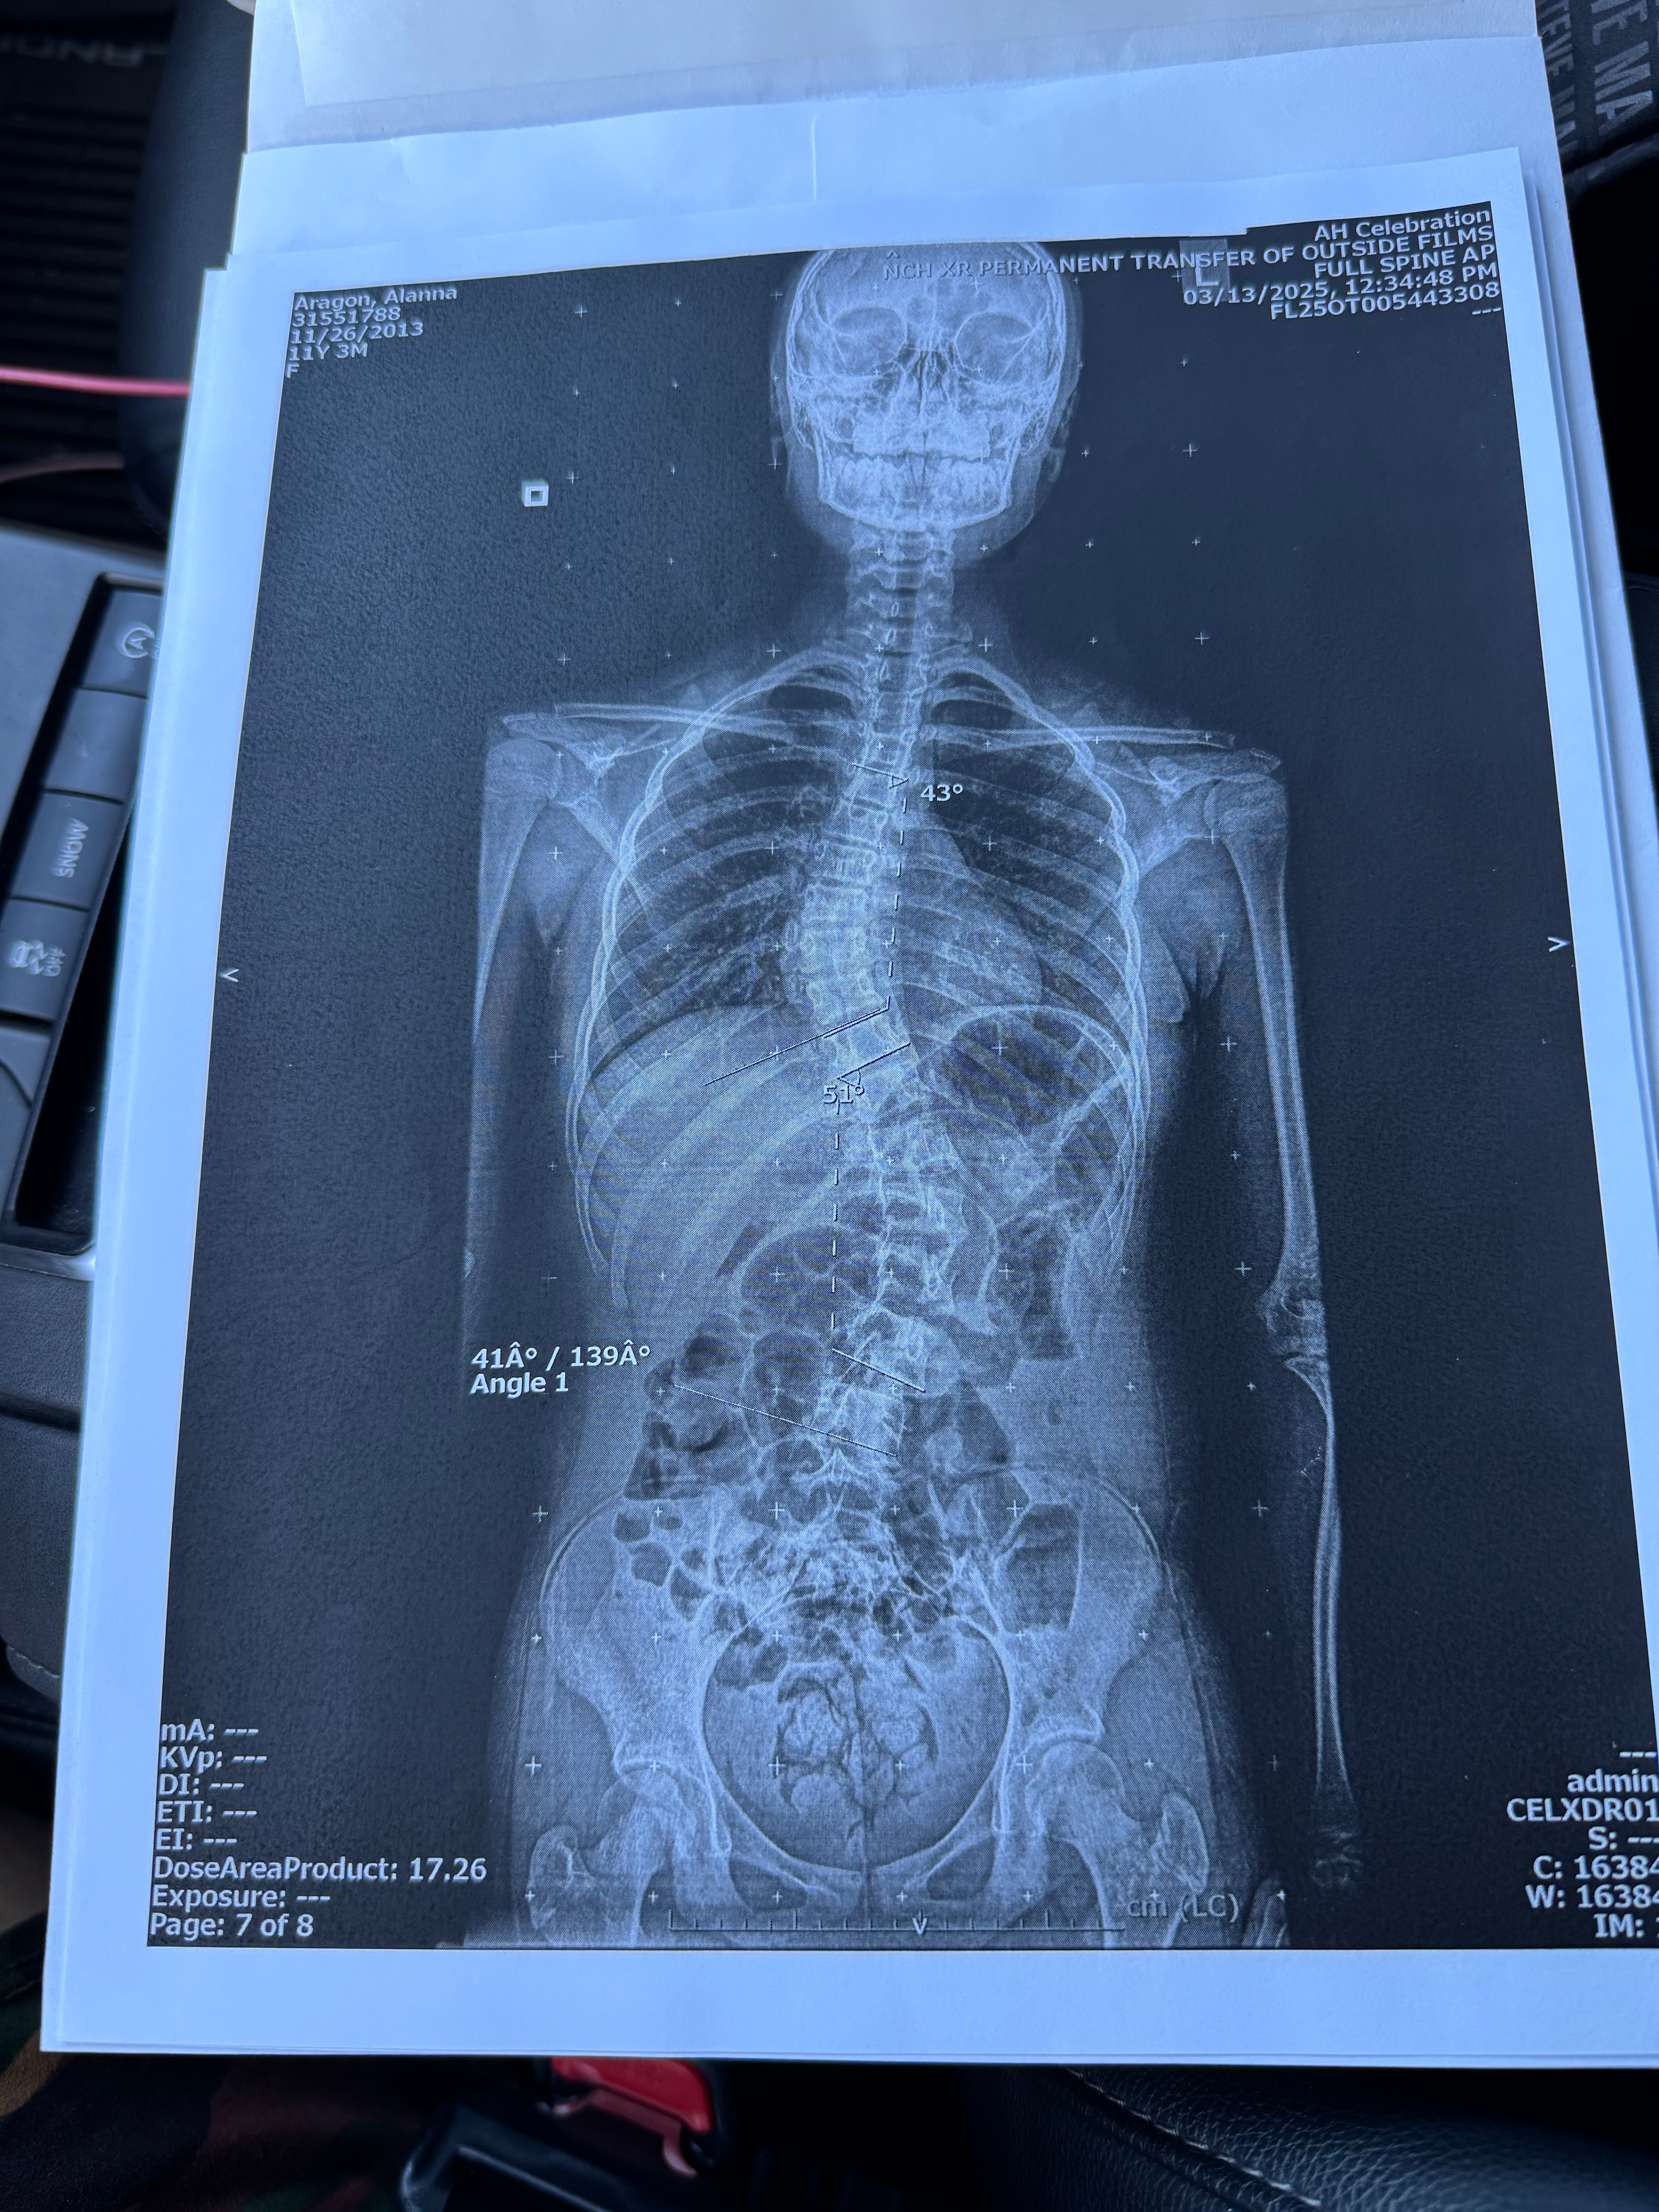

On May 14, she had an appointment with the orthopedic because of her scoliosis condition. That day, they gave me the news that she needs surgery. Her condition is severe.